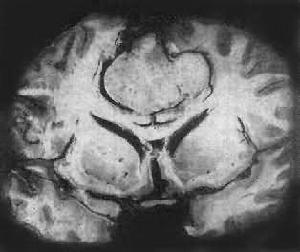

惡性腦膜瘤在CT的表現為腫瘤形態不規則呈分葉狀,可出現蘑菇征邊界不清、包膜不完整信號不均勻周圍水腫明顯,沒有鈣化。增強後腫瘤不均勻強化。腫瘤易侵犯腦組織和顱骨MRI的T1和T2像惡性腦膜瘤都為高信號。有時頸內動脈向腫瘤供血比較明顯。